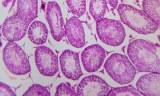

Tissue sections are thin slices of biological tissue prepared for microscopic examination and molecular analysis, fundamental in histopathology, molecular biology, and biomedical research. These sections enable detailed visualization and localization of cellular structures, DNA, RNA, and protein markers, facilitating the study of normal and diseased tissues.

- Detection of tumor markers and disease-specific genes for diagnostics and research.

- Study of gene and protein expression patterns in normal and pathological tissues.